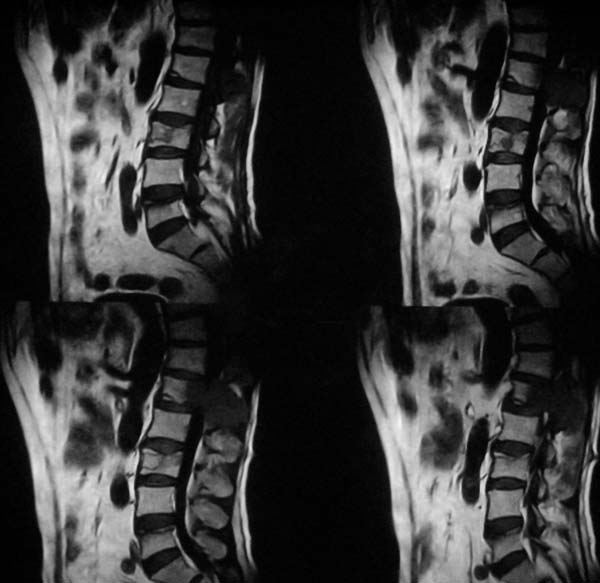

病史特点:

1.中年男性

2.腰疼,双下肢麻木1月。

3.ct 可右肾上腺占位,腰1椎体及附件可见骨质破坏及软组织肿块。

4.mri:腰1椎体及附件t1wi低信号,t2wi高信号。

考虑右侧肾上腺癌骨转移.或右肾上腺及骨均为转移瘤。